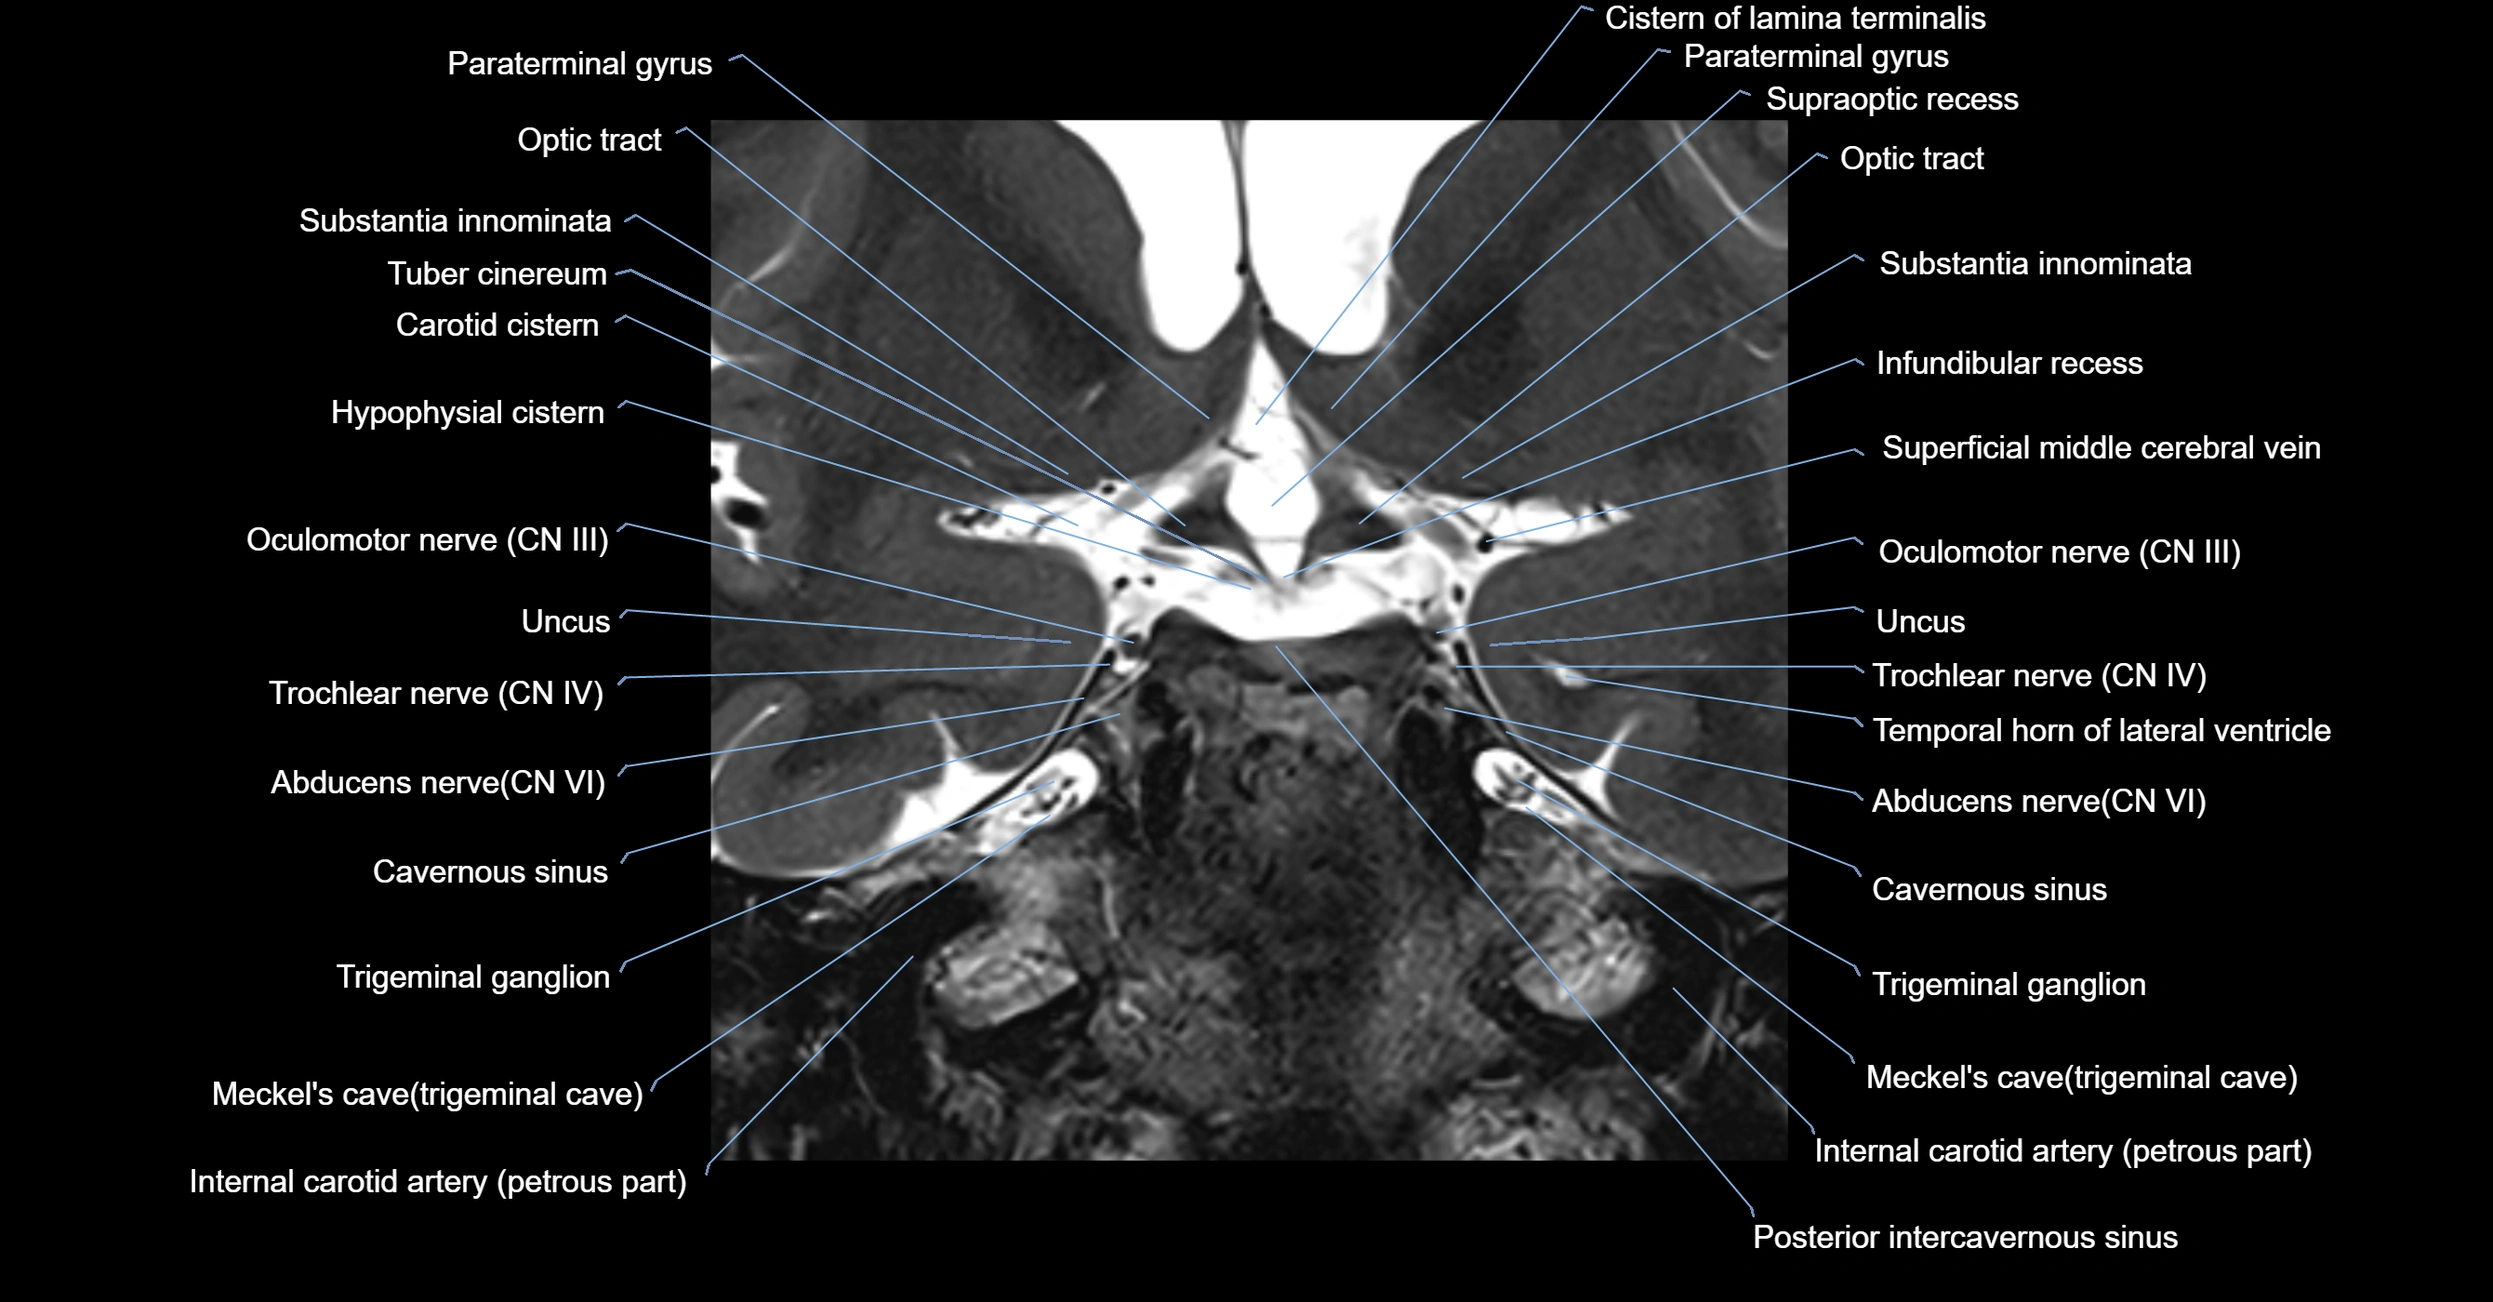

MRI Appearance

-

The abducens nerve is a small, thin, linear structure

Best visualized on high-resolution T2-weighted 3D MRI sequences (e.g., FIESTA or CISS)

Seen as a hypointense (dark) line running from the brainstem at the pontomedullary junction, traversing the prepontine cistern, and entering Dorello’s canal under the petrosphenoidal ligament, then into the cavernous sinus, and finally the orbit

May be challenging to visualize in standard MRI due to its small size

Pathology may be inferred by absence, displacement, or enhancement of the nerve

MRI images